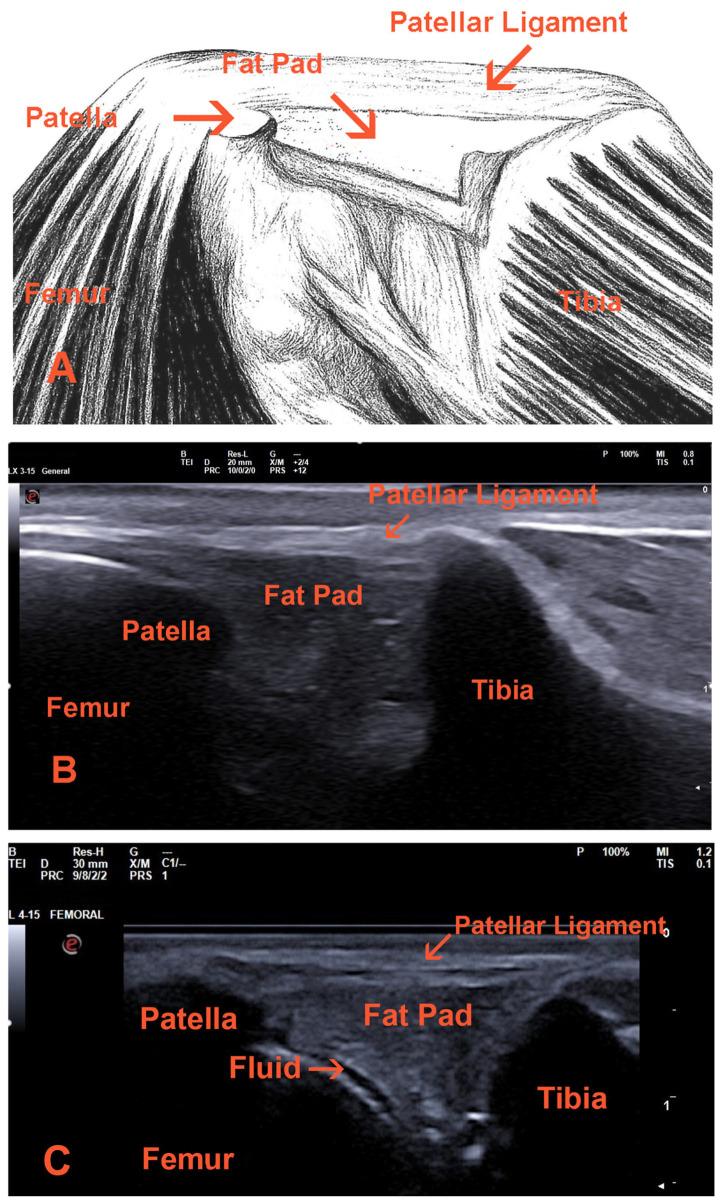

This review presents a comprehensive overview of various ultrasound imaging techniques employed in the evaluation of the canine knee joint. It critically analyzes studies conducted on both human and animal subjects, with a focus on the diagnostic accuracy of B-mode ultrasound, Doppler examination, contrast-enhanced ultrasound, and elastography in both normal and pathological conditions. The review underscores the necessity of strict adherence to the protocols of each ultrasound modality and emphasizes the importance of a thorough understanding of the anatomical region to achieve optimal outcomes. The findings suggest that these ultrasound techniques can significantly enhance the diagnostic process, providing valuable insights into anatomy, size, blood supply, and tissue elasticity. Additionally, in cases where advanced imaging modalities such as computed tomography (CT) or magnetic resonance imaging (MRI) are cost-prohibitive or less accessible, ultrasound serves as a reliable alternative, delivering high diagnostic accuracy and critical information regarding mechanical changes in the joint and neovascularization.

本综述全面概述了用于评估犬膝关节的各种超声成像技术。它批判性地分析了针对人类和动物受试者进行的研究,重点关注B型超声、多普勒检查、超声造影和弹性成像在正常和病理情况下的诊断准确性。该综述强调了严格遵守每种超声模式协议的必要性,并强调了深入了解解剖区域以获得最佳结果的重要性。研究结果表明,这些超声技术可以显著增强诊断过程,为解剖结构、大小、血液供应和组织弹性提供有价值的见解。此外,在计算机断层扫描(CT)或磁共振成像(MRI)等先进成像模式成本过高或难以获得的情况下,超声是一种可靠的替代方法,可提供关于关节机械变化和新生血管形成的高诊断准确性和关键信息。